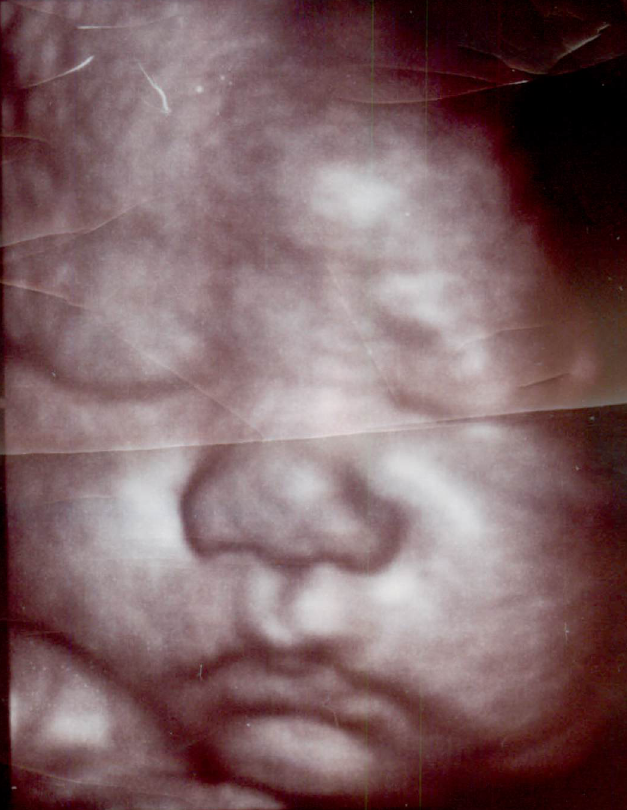

妊娠中期以降になると、顔立ちが良く見えます。

7~8か月以降になると、特に、ふっくらした可愛い顔立ちが見えます。

3D,4Dでは特に赤ちゃんの顔が見えると嬉しいです。普段は

ウトウトと静かに寝ている感じですが、たまに

ニコッとしたり

機嫌の悪そうな顔をすることもあります。又たまに目を開けたり、眼をパチパチすることもあります。